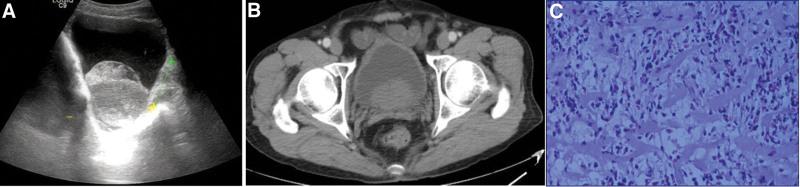

A 72-year-old male patient with symptoms of lower urinary tract obstruction accompanied by hematuria was diagnosed with benign prostatic hyperplasia with bleeding by B-ultrasound and urinary CT examination. After being treated with catheterization, anti-infection and hemostasis, he was selectively treated with transurethral resection of prostate, but he saw a pattern mass on the right back wall of the bladder during the operation. Considering bladder tumor, he removed the lesion and gave pirarubicin for bladder perfusion. However, the postoperative pathological result was EC.

The diagnosis of EC can only rely on pathological examination, and the accurate and positive rate of biopsy can be improved by obtaining muscle tissue as much as possible at the same time of multi-point biopsy.

The clinical manifestations of EC are atypical, the laboratory examination and imaging examination are not specific, and it is difficult to make a definite diagnosis before operation. The diagnosis depends on pathological examination. Transurethral resection of the lesion can obviously improve the positive rate of biopsy while completely removing the lesion, and the combined drug treatment can achieve satisfactory results in a short period of time. Active follow-up after operation is very important to identify the recurrence of the disease and prevent the upper urinary tract function from being damaged.